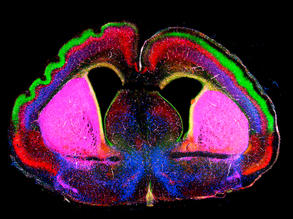

Navigating the Brain